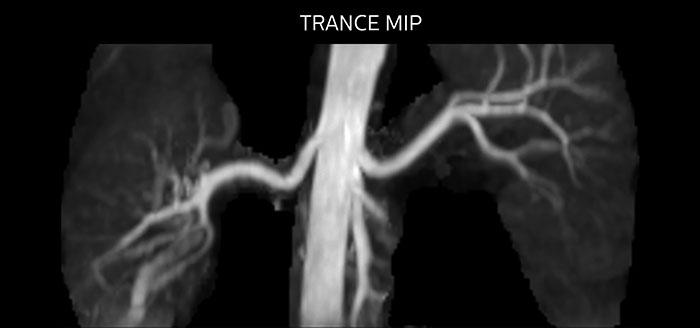

Non-contrast MRA of renal arteries

Imaging the renal arteries without contrast agent on Prodiva 1.5T.